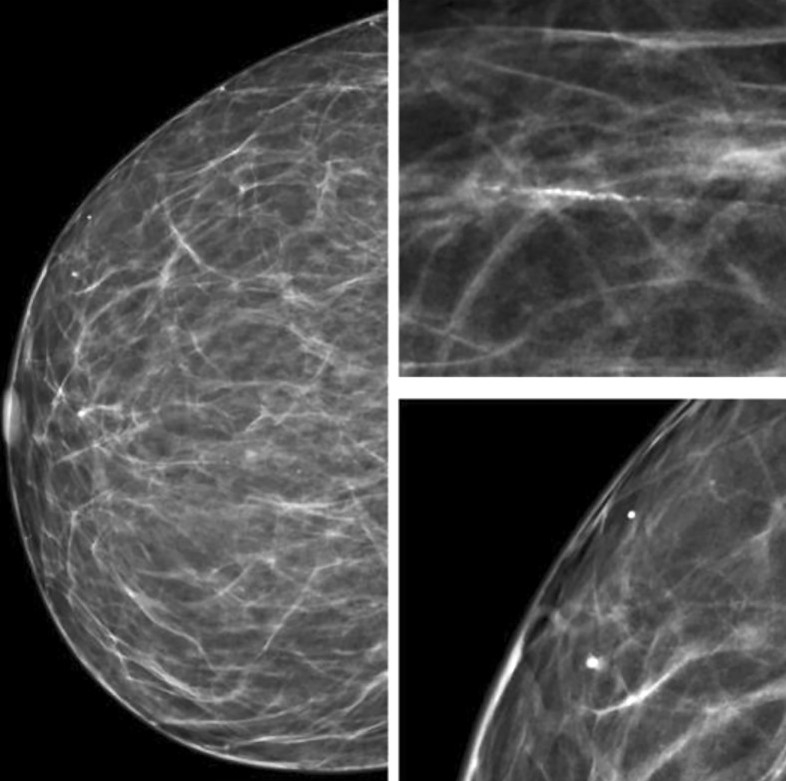

Сосудистые кальцинаты определяются на маммограммах как параллельные гиперденсные линии по ходу стенок сосудов. Их также называют кальцинатами Мёнкеберга, они поражают среднюю оболочку сосуда [13, 14] (Рис.2).